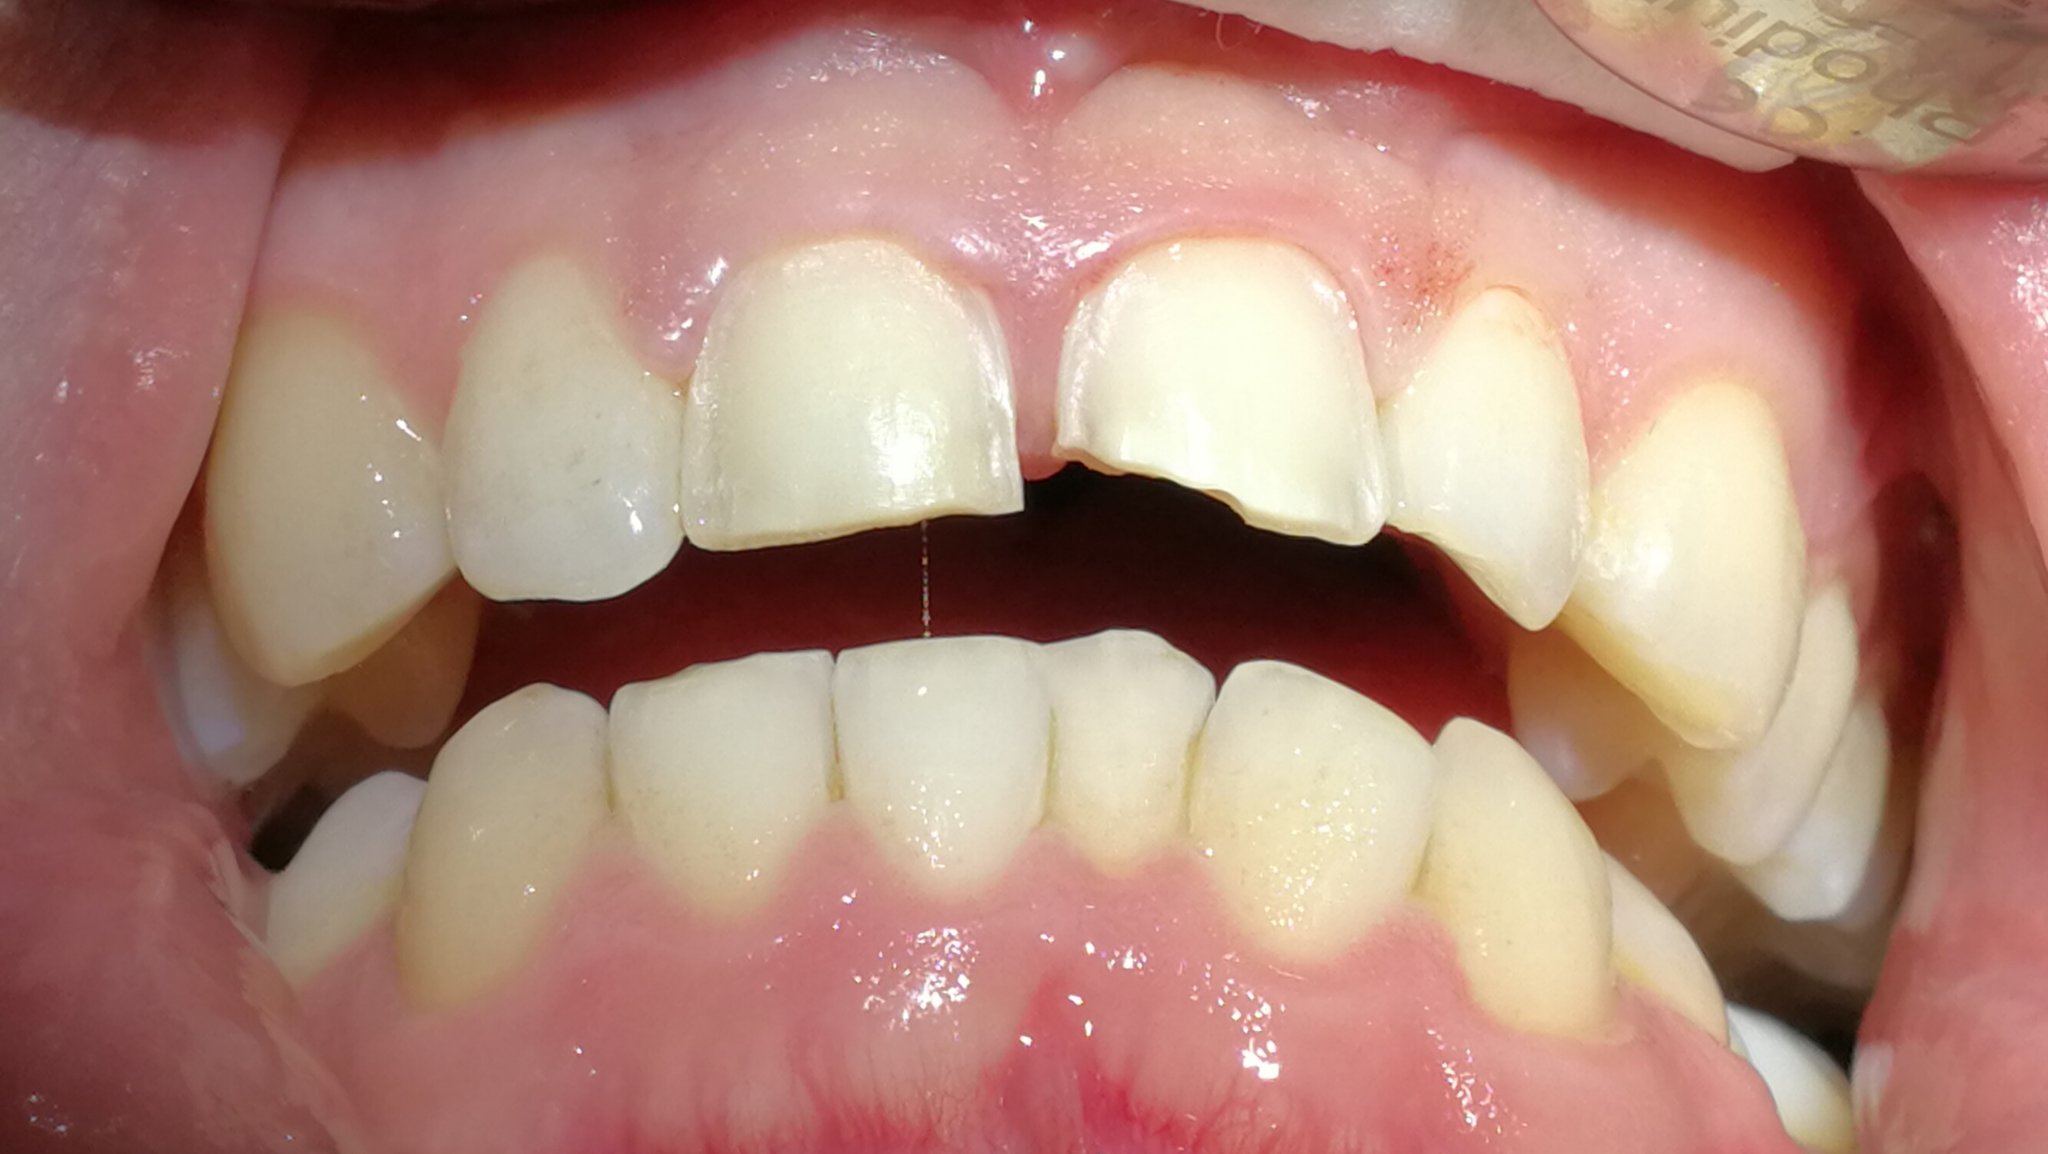

Karies und traumatische Einwirkungen (Zähneknirschen, aus Versehen auf harten Gegenstand beissen und andere Unfälle) können die Zahnhartsubstanz zerstören. Die Reparatur erfolgt in der modernen Zahnmedizin metallfrei, zahnfarben und je nach Grösse des Defektes mit den folgenden Therapiemitteln:

Kompositfüllungen

Kleine Defekte der Zahnhartsubstanz werden mittels einer einfachen Kompositfüllung therapiert (zahnfarbener keramikverstärkter Kunststoff, der im Mund des Patienten

mit Kaltlicht ausgehärtet wird) .